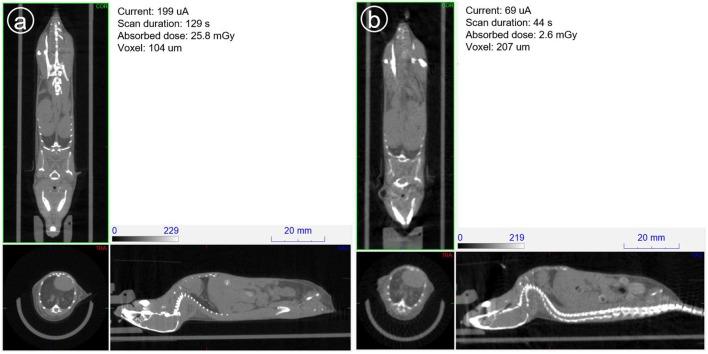

Ionizing radiation constitutes a health risk to imaging scientists and study animals. Both PET and CT produce ionizing radiation. CT doses in pre-clinical imaging typically range from 50 to 1,000 mGy and biological effects in mice at this dose range have been previously described. [F]FDG body doses in mice have been estimated to be in the range of 100 mGy for [F]FDG. Yearly, the average whole body doses due to handling of activity by PET technologists are reported to be 3-8 mSv. A preclinical PET/CT system is presented with design features which make it suitable for small animal low-dose imaging. The CT subsystem uses a X-source power that is optimized for small animal imaging. The system design incorporates a spatial beam shaper coupled with a highly sensitive flat-panel detector and very fast acquisition (<10 s) which allows for whole body scans with doses as low as 3 mGy. The mouse total-body PET subsystem uses a detector architecture based on continuous crystals, coupled to SiPM arrays and a readout based in rows and columns. The PET field of view is 150 mm axial and 80 mm transaxial. The high solid-angle coverage of the sample and the use of continuous crystals achieve a sensitivity of 9% (NEMA) that can be leveraged for use of low tracer doses and/or performing rapid scans. The low-dose imaging capabilities of the total-body PET subsystem were tested with NEMA phantoms, in tumor models, a mouse bone metabolism scan and a rat heart dynamic scan. The CT imaging capabilities were tested in mice and in a low contrast phantom. The PET low-dose phantom and animal experiments provide evidence that image quality suitable for preclinical PET studies is achieved. Furthermore, CT image contrast using low dose scan settings was suitable as a reference for PET scans. Total-body mouse PET/CT studies could be completed with total doses of <10 mGy.

电离辐射对影像科学家和实验动物构成健康风险。正电子发射断层扫描(PET)和计算机断层扫描(CT)都会产生电离辐射。临床前成像中的CT剂量通常在50至1000毫戈瑞之间,此前已描述过该剂量范围内小鼠的生物学效应。小鼠体内[F]FDG的剂量估计在100毫戈瑞左右。据报道,PET技术人员每年因处理放射性活度而受到的平均全身剂量为3 - 8毫希沃特。本文介绍了一种临床前PET/CT系统,其设计特点使其适用于小动物低剂量成像。CT子系统使用了针对小动物成像优化的X射线源功率。该系统设计集成了一个空间束整形器,与一个高灵敏度平板探测器以及非常快速的采集(<10秒)相结合,这使得全身扫描的剂量可低至3毫戈瑞。小鼠全身PET子系统采用基于连续晶体的探测器架构,与硅光电倍增管(SiPM)阵列耦合,并基于行和列进行读出。PET视野轴向为150毫米,横向为80毫米。样品的高立体角覆盖以及连续晶体的使用实现了9%(美国电气和电子工程师协会标准)的灵敏度,可用于低示踪剂剂量和/或进行快速扫描。全身PET子系统的低剂量成像能力通过美国电气和电子工程师协会标准体模、肿瘤模型、小鼠骨代谢扫描和大鼠心脏动态扫描进行了测试。CT成像能力在小鼠和低对比度体模中进行了测试。PET低剂量体模和动物实验证明,可获得适用于临床前PET研究的图像质量。此外,使用低剂量扫描设置的CT图像对比度适合作为PET扫描的参考。全身小鼠PET/CT研究可以在总剂量<10毫戈瑞的情况下完成。